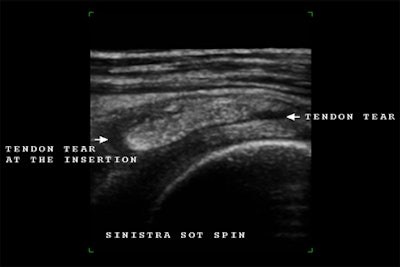

Partial tear

The biceps tendon may have a partial tear, either horizontally or longitudinally. Be sure that the second structure is a part of the biceps tendon and not a loose body within the tendon sheath, giving the appearance of the second tendon in cross-section.

| Multiplanar demonstration of a post-traumatic partial tear on the bursal aspect of the rotator cuff (infraspinatus tendon). The coronal plane and 3D reconstruction demonstrate dramatically the full extent of this tendon tear (indicated by the arrows), which initially on the transverse and longitudinal planes seems less extensive. |

![]() |